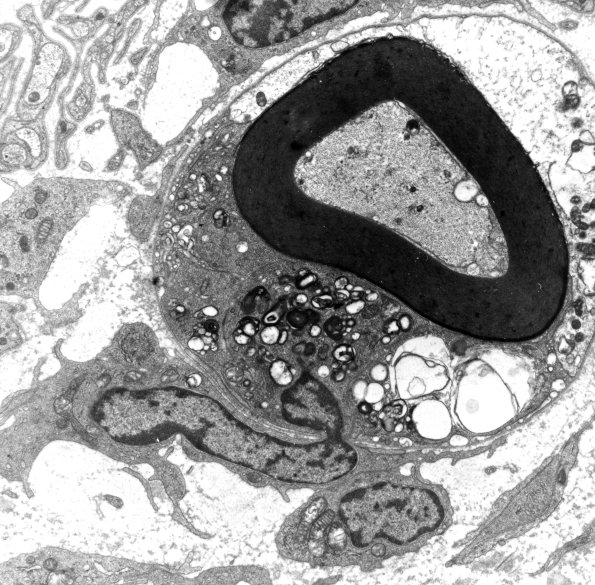

1D2B,C Higher magnifications focusing on the macrophage and an apparent “synapse” (arrow, 1D2C) of a lymphocyte on the macrophage. (electron micrographs)